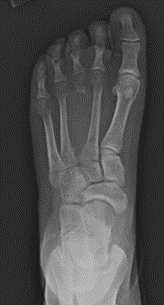

Οι ανευρυσματικές οστικές κύστεις μπορούν να εμφανιστούν σε οποιοδήποτε οστό του σώματος, αλλά συχνότερα βρίσκονται σε περιοχές γύρω από το γόνατο, τον ώμο, τη λεκάνη και τη σπονδυλική στήλη. Συνήθως ανακαλύπτονται με ακτινογραφία. Μπορεί να αναγνωριστούν τυχαία λόγω τραυματισμού ή μπορεί να αναγνωριστούν λόγω πόνου και πρηξίματος στην πάσχουσα περιοχή. Μερικές φορές, οι ανευρυσματικές κύστεις ανακαλύπτονται όταν το οστό σπάσει λόγω της λέπτυνσης και της αποδυνάμωσης της κύστης.

Ενώ μπορεί να εμφανιστούν σε οποιοδήποτε οστό, οι ανευρυσματικές κύστεις βρίσκονται συχνότερα σε:

Ακτινογραφίες. Ο γιατρός σας ή ο γιατρός του παιδιού σας πιθανότατα θα παραγγείλει ακτινογραφίες για να εξετάσει το υποκείμενο οστό.

Η ακτινογραφία συνήθως δείχνει μια οστική βλάβη που έχει αλλάξει το σχήμα και την αντοχή του οστού. Συνήθως, το οστό είναι διευρυμένο με ένα καθαρό κενό στη μέση και ο φλοιός του οστού (ισχυρό εξωτερικό στρώμα) είναι λεπτός.